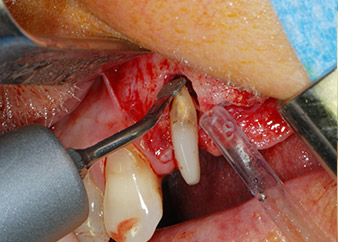

One month later, on the day of surgery, pain and inflammation at tooth 24 were minimal, but mobility of Miller class 2 was still present. After opening the flaps and cleaning the periapical and peri radicular infected tissue, the extent of the bone defect became obvious (Figs. 2 and 3).

At the buccal root, all vestibular and distal bone was missing. Attachment was essentially restricted to the palatal root, underlining the preliminary poor prognosis. Tooth 27 also showed a reduced horizontal attachment and a minimal apical rarefaction (cf. Fig. 1) without clinical symptoms.

However, we maintained our initial plan to retain both teeth as temporary bridge abutments during the six-months osseointegration period of the implants. At reentry, the situation would have to be reassessed. First, in an attempt to manage the endo-perio problem, the remaining root surface was carefully debrided with piezoelectric equipment (Piezomed, W&H, used with the spatula-shaped insert S1, originally designed for erosion of the lateral sinus wall) (Fig. 4).